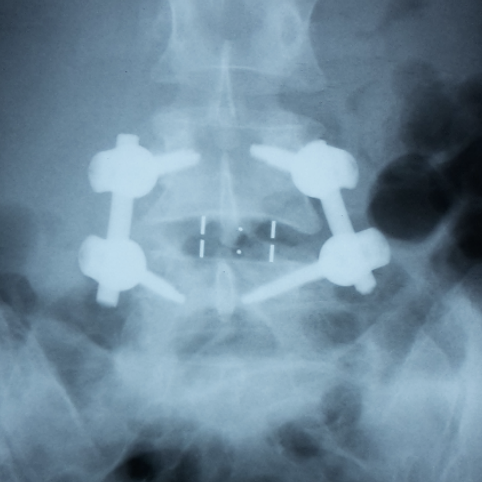

Radiografii din incidenţa laterală preoperator si postoperator ale unui pacient cu spondilolistezis L3-L4 si stenoza lombara multietajata ce a suferit o intervenţie chirurgicală de decompresie şi fuziune intercorporeala anterioara si laterala retroperitoneala cu cage-uri si fixare cu şuruburi pediculare L3-S1. Pe imaginea postoperatorie se observa corectia spondilolistezisului, refacerea lordozei lombare fiziologice, decompresia foraminala indirecta prin cresterea diametrului gaurilor de conjugare.